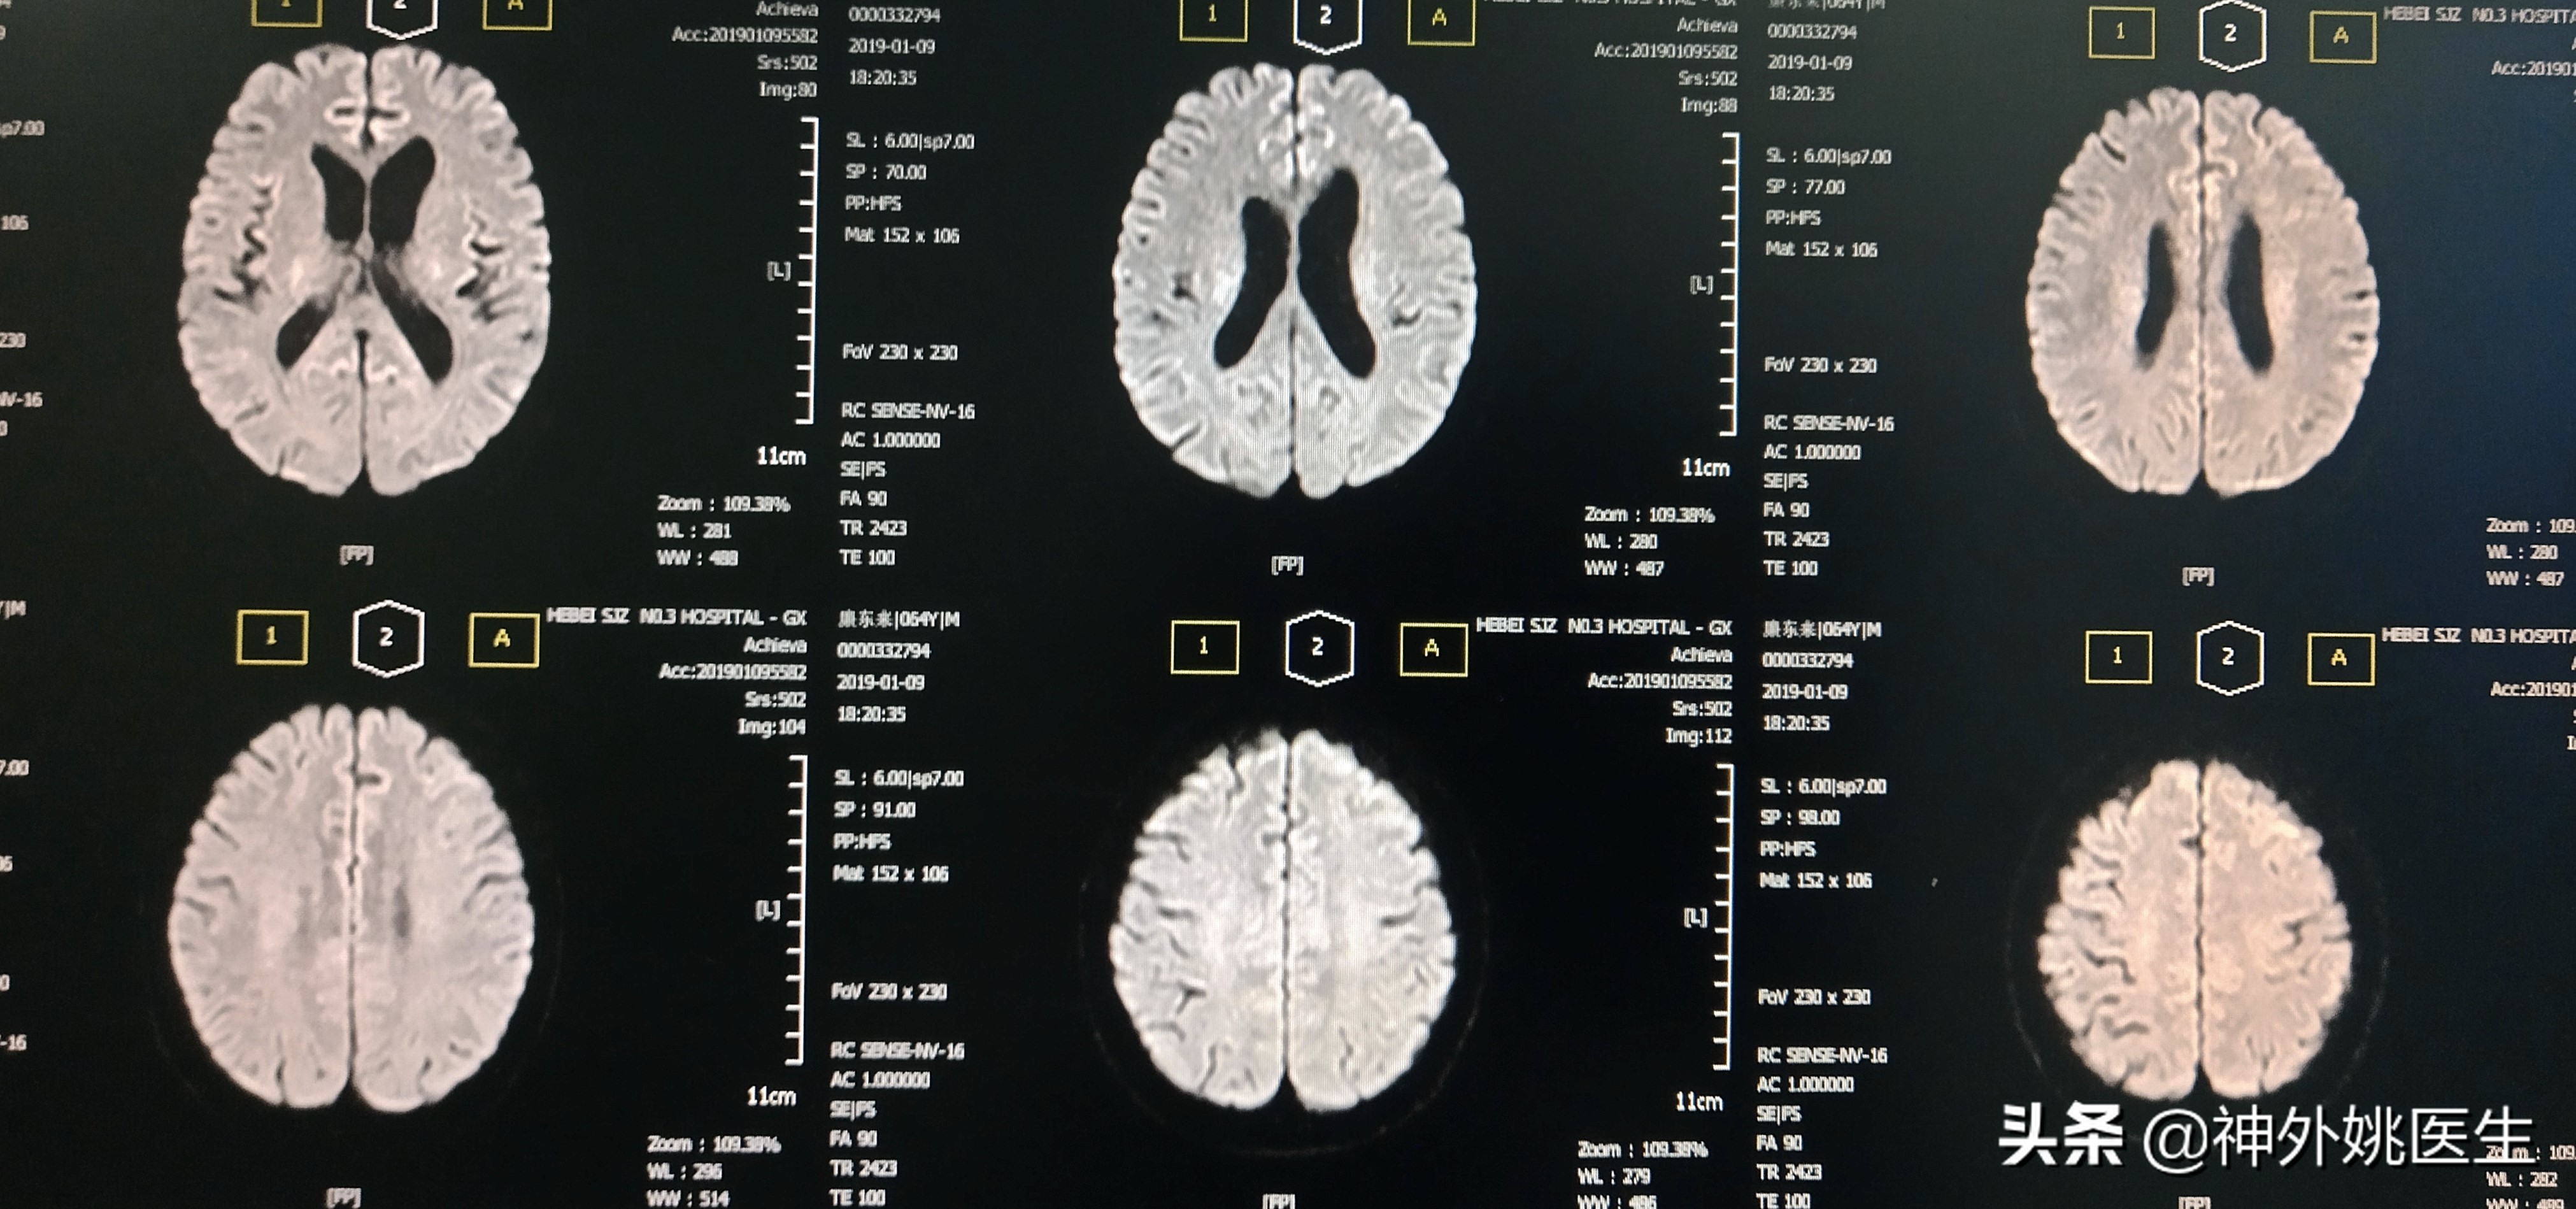

患者廉XX,男性,64岁。主因头痛、头晕,伴右侧肢体无力半年,加重2个月入院。既往“肺腺癌”病史3年,行靶向药物治疗。无“高血压、糖尿病、慢性胃炎”病史。1年前行“腰椎椎体成形手术”。查体:Bp124/91mmHg 神清,语利。双瞳孔正大等圆,对光反射灵敏。左侧肢体肌力5级,右侧肢体肌力5-级。双侧Babinski's征(-)。脑血管彩超示:双侧颈动脉内膜增厚伴斑块形成(多发),左侧颈内动脉起始部狭窄(79-99%)。头MRI+MRA检查:1.双额顶叶及右基底节区缺血灶。2.右颈内动脉虹吸段开窗畸形;左大脑前动脉A1段稍纤细。(图1)颈椎CT示:1、颈椎多发异常密度影,考虑转移瘤;2、颈5/6椎间盘左后突出,椎管狭窄;颈椎骨质增生,排列不稳;4、项韧带钙化。颈部MRI+MRA检查示:1、颈3/4、4/5、5/6、6/7椎间盘突出。2、颈3/4、6/7水平水平椎管狭窄。3、颈椎骨质增生。4、左侧颈内动脉起始部狭窄。(图2)

图1 头MRI示双额顶叶及右基底节区缺血灶。